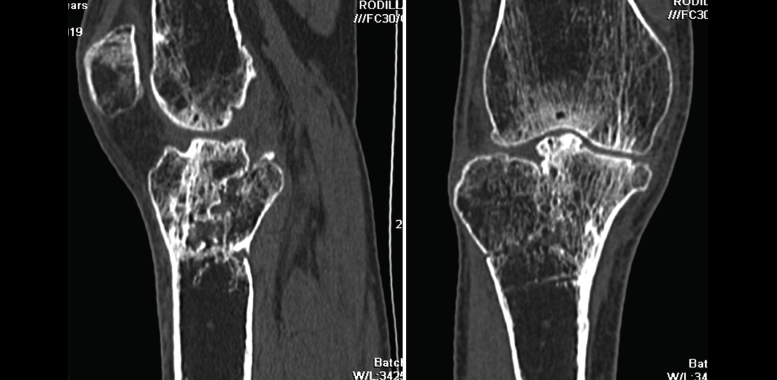

1. Fracturas

Es esencialmente útil en la valoración de los trazos de fractura, de su extensión, del escalón intraarticular y el desplazamiento. También es importante en la planificación del tratamiento de las fracturas intraarticulares complejas.

Los nuevos equipos, con múltiples detectores, permiten realizar cortes finos (submilimétricos) y reconstrucciones en cualquier plano del espacio o tridimensionales (3D) de gran calidad, que facilitan la valoración de estas lesiones(7).

1.2. Tibia (Figura 20)

Figura 20. Corte de reconstrucción coronal de tomografía axial computarizada de rodilla: fractura de ambas mesetas tibiales.

La pseudoartrosis se define cuando, transcurridos al menos 6 meses desde la fractura, no se produce su consolidación y se evidencian muy pocos o ninguno de los signos de evolución radiográfica (Figura 22).

Figura 22. Corte de reconstrucción coronal y sagital de tomografía axial computarizada de rodilla: fractura metafisoepifisaria tibial sin consolidación después de 6 meses.

2.3. Retardo de la consolidación

El retardo de la consolidación es un enlentecimiento de la velocidad esperada (de 3 a 6 meses) del proceso de consolidación de una fractura, pero esta llegará a producirse de forma normal y definitiva (Figura 23).

Figura 23. Corte de reconstrucción coronal y sagital de tomografía axial computarizada de rodilla: fractura de epífisis proximal tibial con puente óseo insuficiente por retraso de la consolidación.

2.4. Consolidación viciosa

Se produce cuando los fragmentos consolidan en mala posición, con deformidades que alteran el eje del miembro inferior (Figura 24).

Figura 24. Corte de reconstrucción sagital y coronal de tomografía axial computarizada de rodilla: consolidación viciosa de la epífisis tibial proximal.